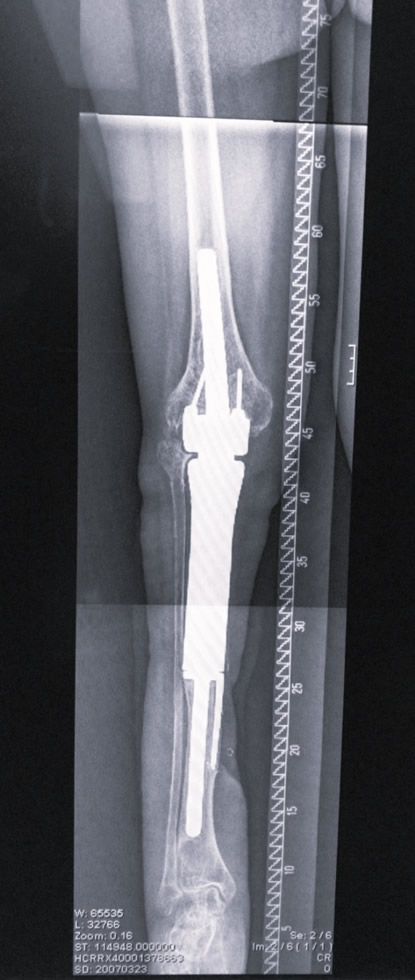

Diagnóstico: Prótesis oncológica de rodilla infectada y expuesta

Paciente de 41 años con antecedentes de osteosarcoma de rodilla previamente intervenida con una prótesis oncológica. La prótesis está infectada, expuesta y en una extremidad lesionada por la radioterapia. La amputación es el único tratamiento que le han recomendado.

- Megaprótesis oncológica de rodilla infectada

- Defecto masivo articular con exposición de la prótesis

Paso 1: Retirada de prótesis, espaciador y cobertura estable

Retirada de la prótesis infectada. Colocación de espaciador de metacrilato con antibióticos y cobertura del defecto con transferencia microvascular ALT.

Paso 2: Retirada del espaciador y reconstrucción de rodilla con articulación del tobillo

Paso 3: Reconstrucción del defecto de tobillo con peroné microvascular

03. Resultado

El resultado funcional fue excelente con preservación de la pierna. La paciente pudo caminar a los 20 meses de la intervención. Una técnica única desarrollada por el Dr. Cavadas que permite evitar la amputación en casos extremos de prótesis oncológica infectada.